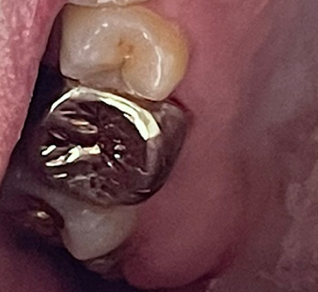

오래전 썩어서 땜질했던 부분이 떨어진 채로 방치하고 살다가 충치가 더 진행되어서 신경을 건드리고 있던 상태였는데요. 4회에 걸쳐 신경치료를 진행했습니다. 구토가 나기도 했지만 의사 선생님이 괜찮다고 그러면서 잘한다고 칭찬도 해주시고 해서 어렵사리 치료 완료했습니다.

저도 말로만 듣던 금니라는 걸 껴 보았습니다. 예전엔 이빨이 통째로 금이라서 금니인가 했는데 크라운 방식으로 씌우는 것이더군요. 처음에는 뭔가 이가 꽉 안 다물어지는 느낌이 들었었는데 의사 선생님 말씀처럼 시간이 점점 지나면서 적응이 되더군요. 1년이 지난 지금은 아주 잘 적응해서 이질감이 전혀 안 느껴집니다.

신경치료가 끝나고 충치가 있는 어금니 하나인가 더 치료했었네요.